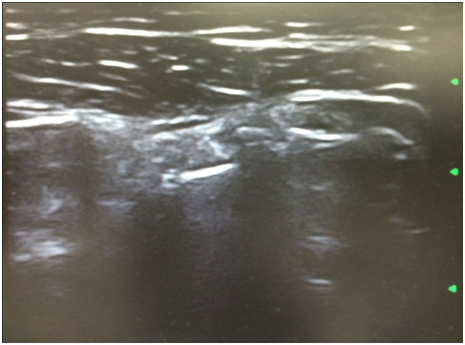

A 49years old male patient presented with a 3years history of progressive pain in the left shoulder, restricted range of movement and crepitation during the active movement of the left shoulder. He is a Non-smoker construction worker. He denied any trauma on the region and has no past medical history of interest for the pathology. He had no active movements above the head of the left shoulder after 40degrees of abduction. On the physical examination the active range of movements was limited, abduction 60º, adduction 40º, flexion 50º, extension 10º, internal and external rotation 20º, all of them were painful with crepitus during moment. We were able o identify rotator cuff sings of rupture and positive findings of subacromial impingement. He had a DASH test score of 52.5 being 0 the least dysfunctional score, and VAS score of 7/10 on a resting position and 10/10 during active range of movements. Plain radiographs of the left shoulder were taken identifying multiple calcification bodies within the articular space (Figure 1). An articular ultrasonography (USG) was ordered finding a complete rupture of the supraspinatus tendon no other tendon or labral abnormality (Figure 2). The differential diagnosis that should be considered are degenerative joint disease, osteochondritis dissecans, synovial sarcoma, chondrosarcoma, rheumatoid arthritis, pigmented villonodular synovitis and osteonecrosis of humeral head.3 The patient underwent a shoulder arthroscopy on a beach chair position under general balanced anesthesia. A standard anterior and posterior portals were used, finding a normal labrum tissue, a complete rupture of the supraspinatus tendon, multiple loose bodies and synovitis (Figure 3). The treatment consisted in loose bodies extraction, synovitis resection and the supraspinatus tendon rupture was reattached after debridement of the footprint with two 5.5mm Healix anchor (Mitek Sports Medicine; Raynham, MA) and two 3.5mm Push-Lock anchors (Arthrex; Naples, FL) using a modified Suture bridge technique. We had a positive confirmation from one of the loose bodies sent to the pathology department. The patient was discharged from the hospital the next day after the surgical procedure. A shoulder immobilizer with an abductor cushion had to be worn for 8 weeks. Starting physical therapy on week two with passive pendulum movements at home, and finally active movements and muscular strengthening at week 6. After 12weeks he started doing his normal life activities still no sport related activity. At the sixth post operatory month he had a final DASH Score of 18.2 and a resting VAS of 0/10 and during physical activity of 1/10. With active range of movement as followed abduction 100º, adduction 40º, flexion 120º, extension 25º, internal and external rotation 35º.

Figure 2 Supraspinatus tendon ultrasonography with a complete rupture.